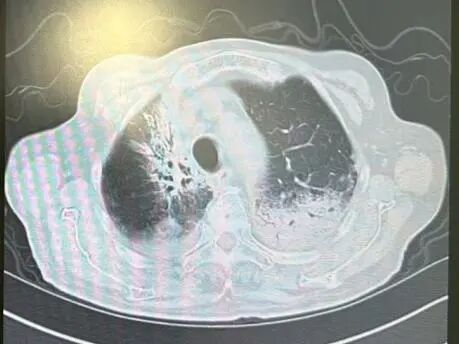

内容提要 近日,市第二人民医院呼吸与危重症医学科宋刚主任团队,成功救治一名98岁高龄、患有罕见隐源性机化性肺炎(COP)的患者。面对高龄、病情复杂、诊治风险高等重重困难,团队凭借精湛医术与丰富经验,帮助老人转危为安,再次彰显了科室在危重症救治领域的强大实力。 挑战一:高龄禁区,敢为人先 患者因发热、咳嗽,伴乏力、气短、喘息等症状来院,此前在当地诊所使用多种抗生素均无效,病因成谜。要明确诊断,支气管镜检查是关键一步,但对近百岁老人而言,此项操作犹如踏入“生命禁区”,风险极高。宋刚主任团队没有退缩,在全面评估、周密预案、充分沟通的基础上,凭借丰富经验成功实施检查,为后续治疗打开了至关重要的突破口。 治疗前患者肺部CT影像 挑战二:罕见病症,迷雾重重 检查结果指向一种罕见疾病——隐源性机化性肺炎(COP)。此病本就少见,好发于50~60岁人群,在近百岁老人中发生更是极为罕见。更为棘手的是,患者还伴有胸腔积液。COP通常表现为发热和肺部影像上的“游走性”阴影,很少合并胸腔积液,这使得诊断工作如雾里看花,难度倍增。 挑战三:病菌分辨,生死抉择 诊断刚明,新的考验接踵而至:患者标本中检出了根毛霉菌。COP的核心治疗是糖皮质激素,若根毛霉菌是致病菌,激素可能引发真菌扩散,用药无疑将导致致命风险。因此,辨别其是“定植菌”还是“致病菌”,成为治疗成败的关键。 宋刚主任团队凭借丰富的临床经验和严谨的诊疗思维,结合患者肺部影像特征、症状及化验结果,综合判断认为该霉菌属于定植菌,从而排除了治疗障碍,确保了后续用药安全。 精心施治,百岁老人转危为安 在后续治疗中,团队如履薄冰,精细平衡抗凝与激素治疗带来的出血、感染等风险,制定个体化方案。经过精心治疗与护理,老人肺部病灶显著吸收,各项指标恢复正常,最终康复出院。 治疗前后肺部CT影像对比,左侧为治疗后,右侧为治疗前。 此次成功救治,充分体现了市二院呼吸与危重症医学科在复杂疑难呼吸道疾病及危重症领域的综合救治能力。面对高龄高风险患者,团队始终以患者为中心,在风险与疗效间精准把握,用技术与责任守护每一位患者的呼吸健康。 人民医院 人民名医 宋刚 主任医师 ·葫芦岛市第二人民医院呼吸与危重症医学科主任 ·辽宁省生命科学学会东北呼吸与危重症医学(PCCM)分会辽宁省基层委员会副主任委员 ·辽宁省细胞生物学学会放射粒子治疗专业委员会理事 ·辽宁省抗击新冠肺炎疫情先进个人 ·辽宁省预防医学会第一届吸烟相关疾病防治专业委员会委员 ·葫芦岛市劳动鉴定委员会专家库成员 ·葫芦岛市医学会呼吸内科学分会第三届委员会副主任委员 专业特色:擅长呼吸系统疑难及急危重患者的救治,如急慢性支气管炎、支气管哮喘、慢性阻塞性肺疾病、肺炎、肺栓塞、肺癌、间质性肺疾病、睡眠呼吸暂停综合征等,尤其擅长有创无创机械通气、支气管镜下相关检查及治疗(TBNA、气道支架置入术、球囊扩张等)、全肺灌洗术等领先技术,发表国家级期刊多篇。 出诊时间:每周二、周四全天 出诊地点:门诊二楼东侧35诊室